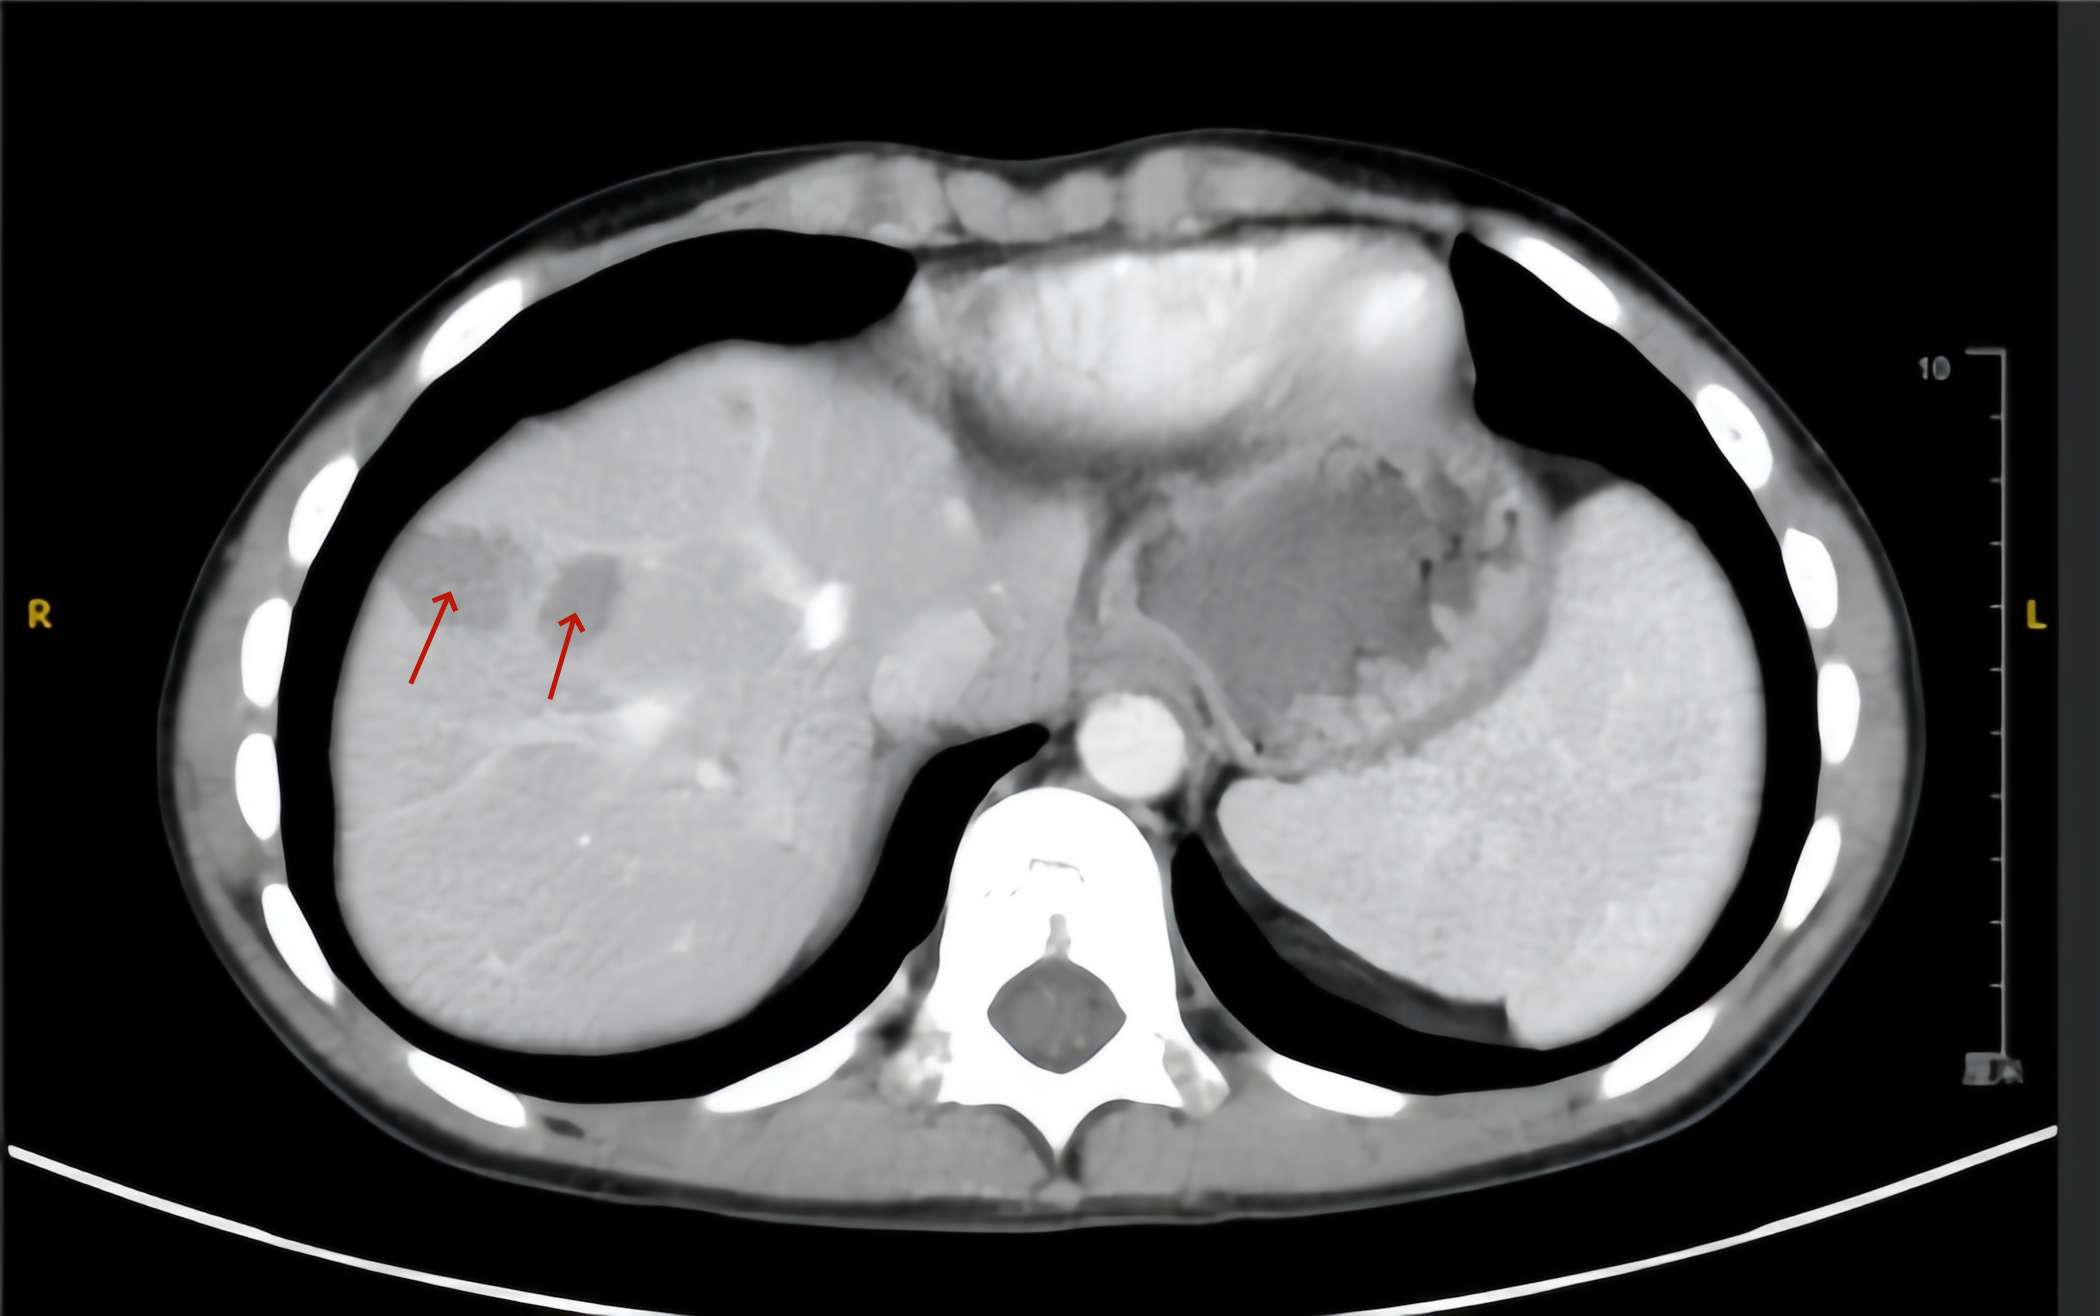

图为小童钇90术前的肝脏影像,箭头处为两处较大的肿瘤

小童再次来到北京清华长庚医院,经肝胆肿瘤MDT讨论后,建议评估行钇90微球介入治疗的可行性。钇90治疗团队经过详细的准备,联合肝胆胰外科、肝胆介入科、核医学科、儿外科和放射科等多学科讨论,最终确定余肝内多发肿瘤可安全进行钇90微球介入治疗,并对肿瘤吸收剂量、肝脏剂量、处方活度进行充分计算。经过周密的术前准备,于2024年10月成功完成钇90微球介入手术,术后即刻PET/CT评估显示肝内多发病灶微球覆盖良好,周围正常组织无明显微球分布,术后患儿无明显不适,复查肝功能无明显异常,第2天即出院。